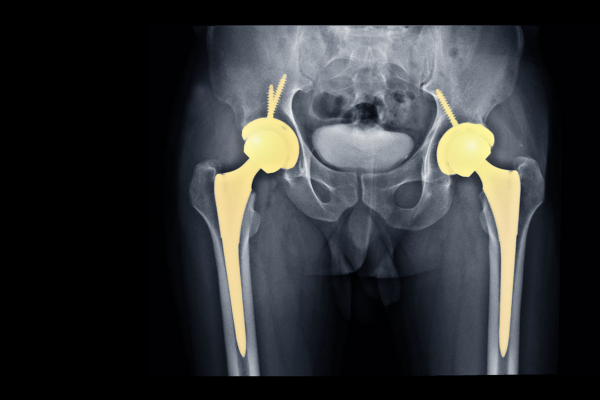

Total Hip Replacement

Read More